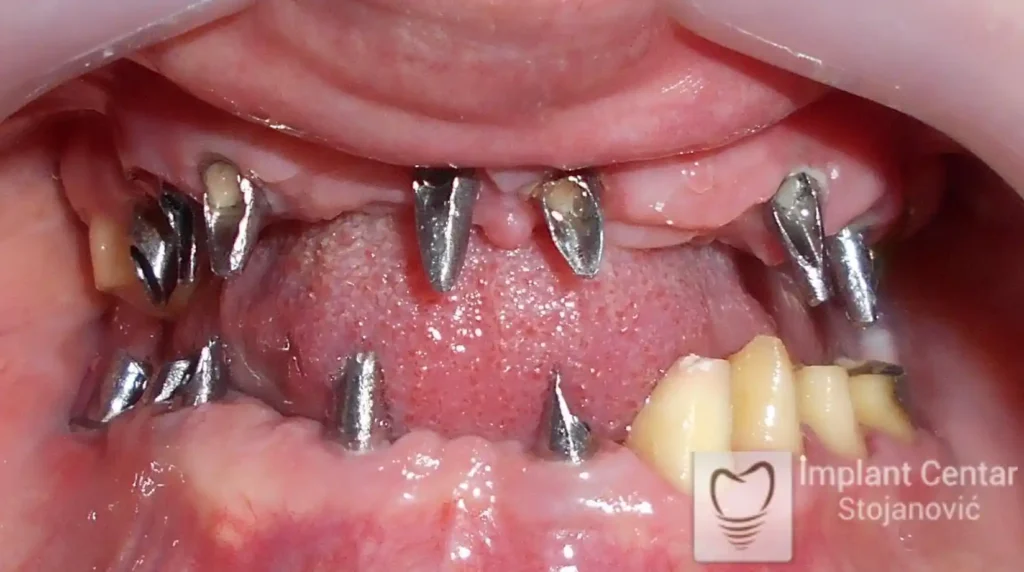

Na slikama 1, 2, 3 , 4  i  5 prikazan je izgled pacijenta pre početka terapije. Nakon detaljne kliničke i radiološke analize, doneta je odluka o vađenju zuba loše biološke vrednosti, dok su bezuba polja sanirana ugradnjom dentalnih implantata.

Nakon ugradnje implantata i pripreme preostalih zuba, pacijentu su izrađene fiksne privremene krunice, čime je postignut eugnatan zagriz već nakon jednog dana (slika 8, 9 i 10). Tokom perioda osteointegracije, pacijent se postepeno privikavao na novi položaj vilica i zagriz.

Po završetku perioda integracije, izrađeni su definitivni cirkonijum-keramički mostovi, čime je postignuta potpuna rekonstrukcija zagriza, kao i značajno poboljšanje estetike i oralne funkcije (slika 12, 13, 14 i 15).